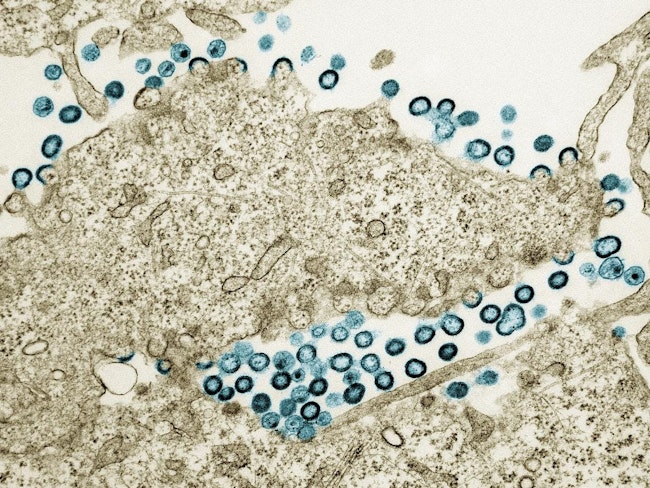

| | | | | | A single laboratory-based HIV viral load test used by U.S. clinicians who provide people with long-acting, injectable cabotegravir (CAB-LA) HIV pre-exposure prophylaxis (PrEP) did not reliably detect HIV in a multi-country study. |